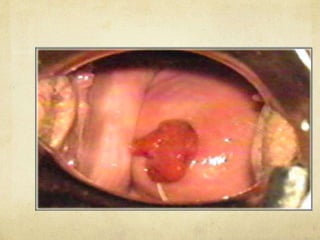

EXAMEN CON

ESPECULO

Permite visualizar la presencia de infecciones

que pueden producir un moco purulento

inadecuado para la penetración de

espermatozoides.

También se pueden apreciar pólipos de diversos

tamaños que sobresalen por el orificio cervical

externo y pueden producir un obstáculo

mecánico y sinusorragia que incomoda las

relaciones sexuales